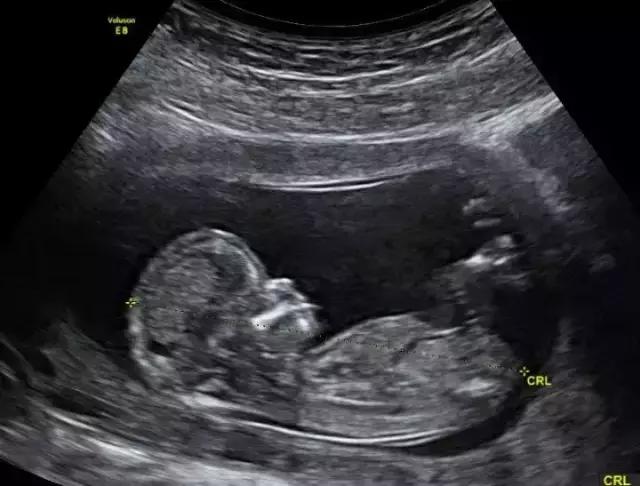

6、超声扫描仪

从1959年开始,澳洲超声研究所开始花下大量的人力物力研究超声波,经过多年的细心研究和实验,终于研究出了一种利用超声波:这种超声波发射后可以在身体软组织上反弹,并将此信息成像展示在显示屏上。

这一发现永远改变了产前保健的情况,让医生及怀孕的父母在不经过X光的情况下,也能看到胎儿的情况。此项技术在1976年推广,如今也被用于诊断乳房、腹部等其他医学问题。